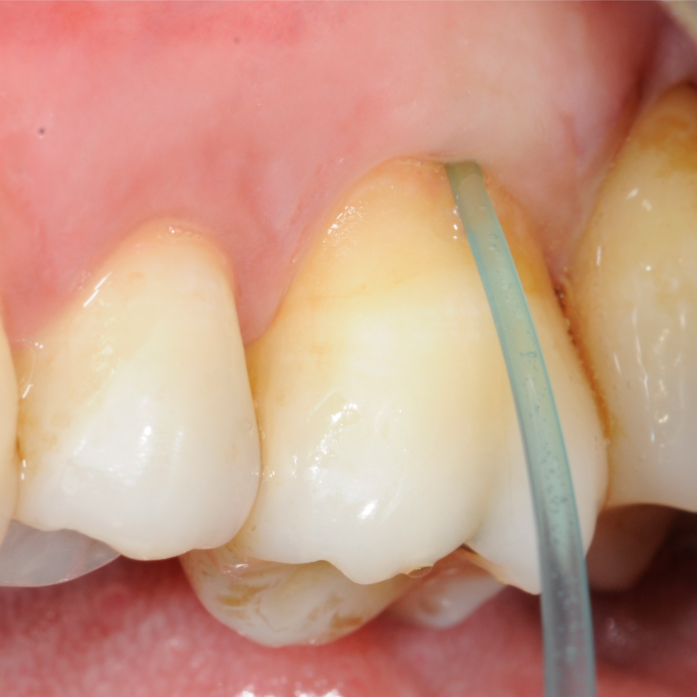

Case Report

Anwendung der minimal-invasiven Socket Seal-Technik Dr. Johannes Petschelt M.Sc., Dr. Andreas Petschelt |